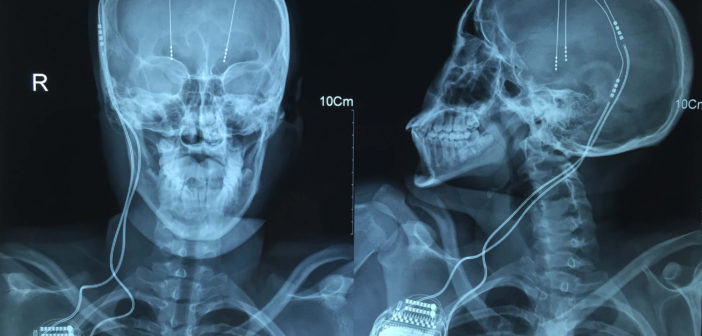

La cirugía –abreviaba DBS en inglés por deep brain stimulation– les entrega mejor movilidad a los sujetos, disminución del temblor y menor rigidez, lo que permite que personas que habían perdido independencia y oportunidades de trabajo, puedan retomar su vida. El pionero nacional en ejecutar este procedimiento fue la Clínica Alemana y su jefe de servicio de neurocirugía, el Dr. Felipe Valdivia, explica el proceso con electrodos de la siguiente manera: “En el modelo de Parkinson nosotros sabemos que cuando tú tienes Parkinson hay ciertos núcleos que están sobreexcitados. Lo que haces básicamente es inhibir esta sobreestimulación con una estimulación eléctrica de alta frecuencia sin generar lesión”.

Los especialistas describen el estimulador cerebral profundo como una especie de marcapaso que produce una alteración al nivel del circuito afectado. “Cuando uno apaga el estimulador se acaba la lesión y el paciente vuelve a estar como estaba antes. Puedes aumentar el voltaje, la cantidad de polos que se está estimulando y se mantiene al paciente mucho más tiempo porque la enfermedad sigue progresando y uno puede ir manipulando la estimulación, aumentándola”, asegura el Dr. Pedro Vázquez, neurocirujano del Hospital Clínico Universidad de Chile José Joaquín Aguirre.